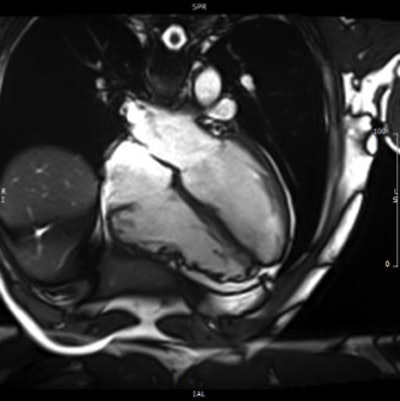

Above and below: Patient with ARCV/D confirmed with CMR. All images courtesy of Dr. Antonio Amadu.They identified 124 patients with suspected ARCV/D. This group had a median age of 40 years (± 16, range 17 to 77 years), representing 5% of total CMR referrals.

Amadu and colleagues from both institutions including Dr. C.L. Rodrigues, Dr. A. Dastidar, Dr. G.B. Meloni, Dr. M. Conti, Dr. Chiara Bucciarelli-Ducci et al, performed CMR on a 1.5-tesla scanner (Magnetom Avanto, Siemens Healthcare). A comprehensive protocol, including long and short-axis axial cine images and late gadolinium enhancement, was used in all patients.

In all, four of the 124 patients met the CMR criteria for ARCV/D. Of these, three had major criteria and one had minor criteria, for a prevalence of 3%.